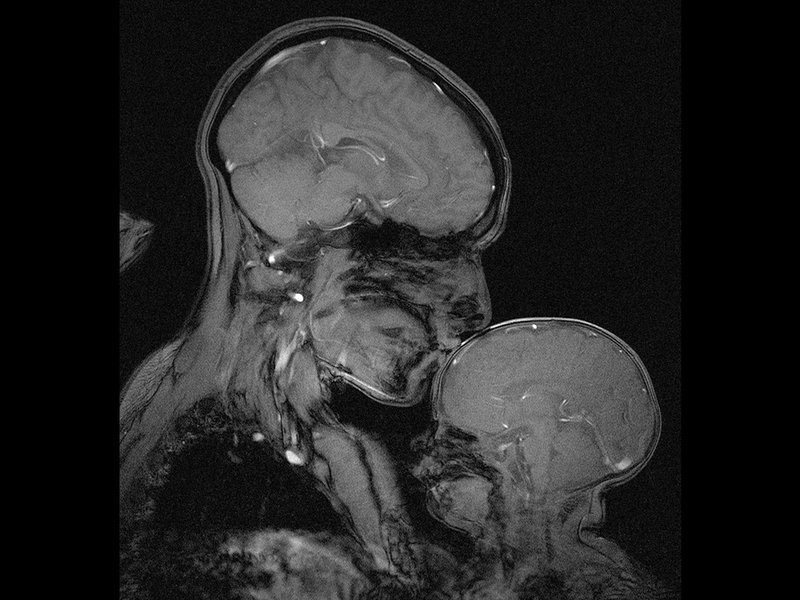

This great magnetic resonance image (MRI) of a mother and her baby curled up together, a symbol of close human bonding, was taken in April 2015. Such a picture needs several minutes to capture, a move of only a millimeter leaving a blur on the screen, so the mother and the child have to hold their pose. The baby had finally fallen asleep pressed against his mother’s chest, allowing the machine to see what happens inside their brains.

Interestingly, this image that is probably the first magnetic resonance image showing a mother and her child, was not made for medical purposes, not even for science. “We made this one because we wanted to see it,” says Rebecca Saxe, an associate professor of cognitive neuroscience in the department of Brain and Cognitive Sciences at Massachusetts Institute of Technology (MIT).

Image: MIT